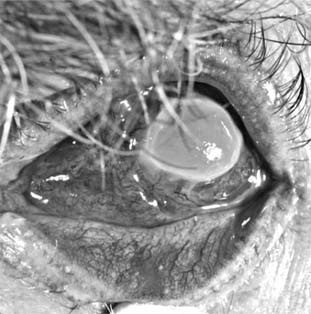

Fungal ulcers are indolent and have a gray infiltrate, often a hypopyon, marked inflammation of the globe, superficial ulceration, and satellite lesions (usually infiltrates at sites distant from the main area of ulceration) (Figure 6-3). The principal lesion-and often the satellite lesions as well-is an endothelial plaque with irregular edges underlying the principal corneal lesions, associated with a severe anterior chamber reaction and a corneal abscess.

Figure 6-3

Figure 6-3: Corneal ulcer caused by Candida albicans.

Most fungal ulcers are caused by opportunists such as Candida, Fusarium, Aspergillus, Penicillium, Cephalosporium, and others. There are no identifying features that help to differentiate one type of fungal ulcer from another.